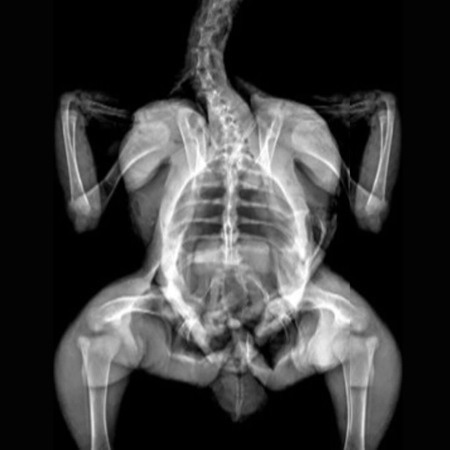

X-Ray Attenuation Image - Rat.

X-Ray Attenuation Image - Rat. Image Credit: Scintica Instrumentation Inc